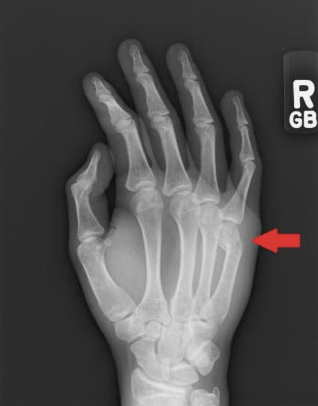

What fracture is this?

Bennett

What is a Bennett fracture?

Longitudinal fracture at base at first metacarpal with fracture line entering the CMP joint